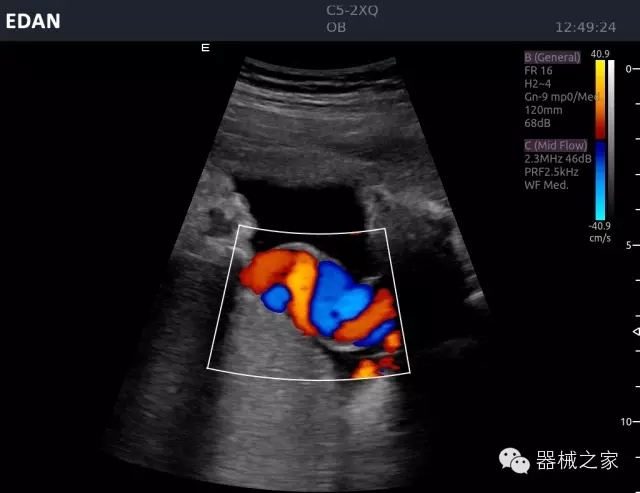

經(jīng)典產(chǎn)品:Acclarix AX8

臨床圖片賞析

睪丸低速血流

臍帶血流

頸動(dòng)脈頻譜

產(chǎn)品特點(diǎn)

·新視界、高效能、新體驗(yàn);

·別具匠心的獨(dú)特設(shè)計(jì)、創(chuàng)新工作流、強(qiáng)大的功能組合以滿足POC圖像的需求;

·15英寸高分辨率顯示器;

·10.1英寸防指紋觸摸屏;

·獨(dú)一無二的觸控式軌跡球;

·超聲模塊的便攜式設(shè)計(jì);

·128物理通道;

·UPS持續(xù)供電;

多項(xiàng)前沿圖像技術(shù)

·復(fù)合成像 波束合成 頻率復(fù)合 噪聲抑制等;

穿刺針增強(qiáng)技術(shù)

·顯著增強(qiáng)針體 清晰識別結(jié)構(gòu)、位置等比鄰關(guān)系;

多種成像模式

·梯形成像 寬景成像 3D成像 特征成像等;

CFDA注冊證編號

·粵械注準(zhǔn)20152230912